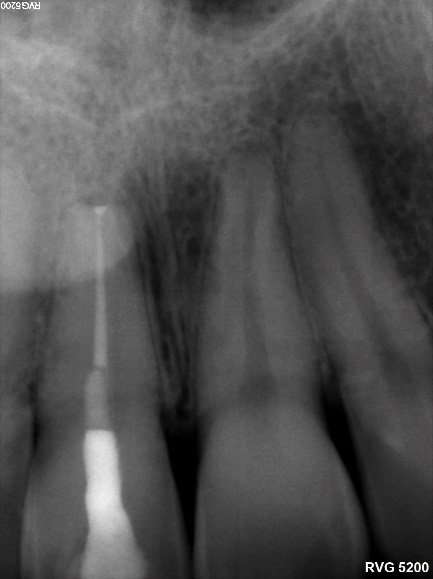

1-Year Follow-Up showing the complete healing of the periapical lesion on teeth #11 and #12

Does Endodontic Treatment with Bioceramic Cements Accelerate the Recovery of Periapical Lesions? A Case Report

BIO-C® TEMP: A new alternative for intracanal medication

Tooth Apexification Using Bioceramic Materials